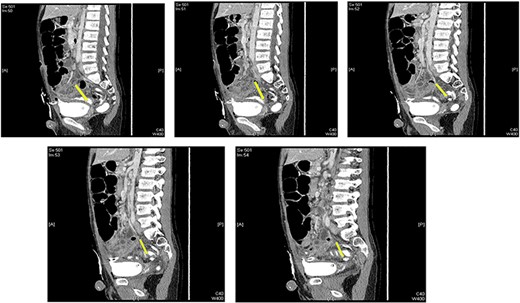

A contrast cystogram was performed on postoperative day 9, and a pelvic scan showed no leak or extravasation of the contrast fluid (Fig. 3). The catheter was removed, and the patient was discharged after successful micturition trials. Follow-up examinations performed 2 weeks and 1 month post-discharge were unremarkable and the patient presented no complaints.

Cystogram performed on postoperative day 8 showed no extravasation of the contrast material.